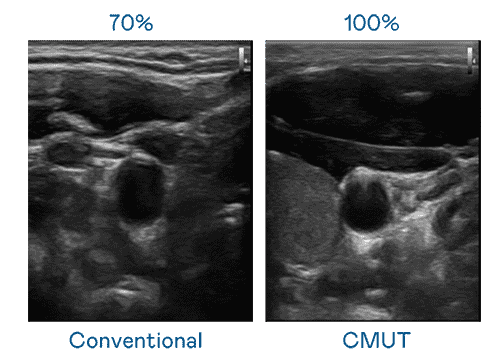

CMUT 技术是一种用电容式微机电元件来产生超音波讯号的技术。。。。与传统 PZT 压电式技术相比,,CMUT 频宽增加 30%,,,更宽频的超音波讯号让影像解析度大幅提升,,,,是实现高影像品质医疗超音波扫描、、、、促进精准医疗发展的关键技术。。

超音波影像的解析度高低,,,首先取决于探头能发出的讯号频宽。。。PG国际 CMUT 可提供高清晰的超音波讯号,,,提供高频宽、、高灵敏度、、影像纹理细节更高的超音波影像,,协助医护人员缩短影像判读时间及利用精准的医疗影像进行诊断。。。。